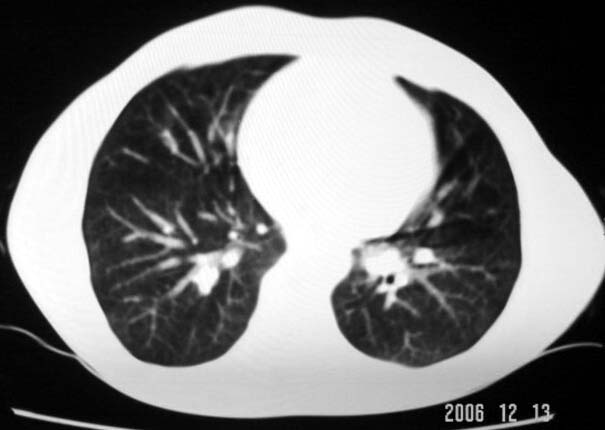

标题: CT5614:外伤病人男,20岁,右上腹痛.余肺野(-)

外伤病人男,20岁,右上腹痛,ct显示:右肺下叶后基地段见斑片状高密度影,密度不均,边界清,考虑1,右肺下叶肺挫伤;2,炎症。

其次,病灶较多并散布在右下肺底,纵肺比例明显小于50%,与膈肌以及后壁胸膜有轻度粘连。且其内密度不均匀,最大的那个结节影里面有较致密密度,胸椎旁似乎还有液平面。也就是说右下肺炎性改变可以肯定。